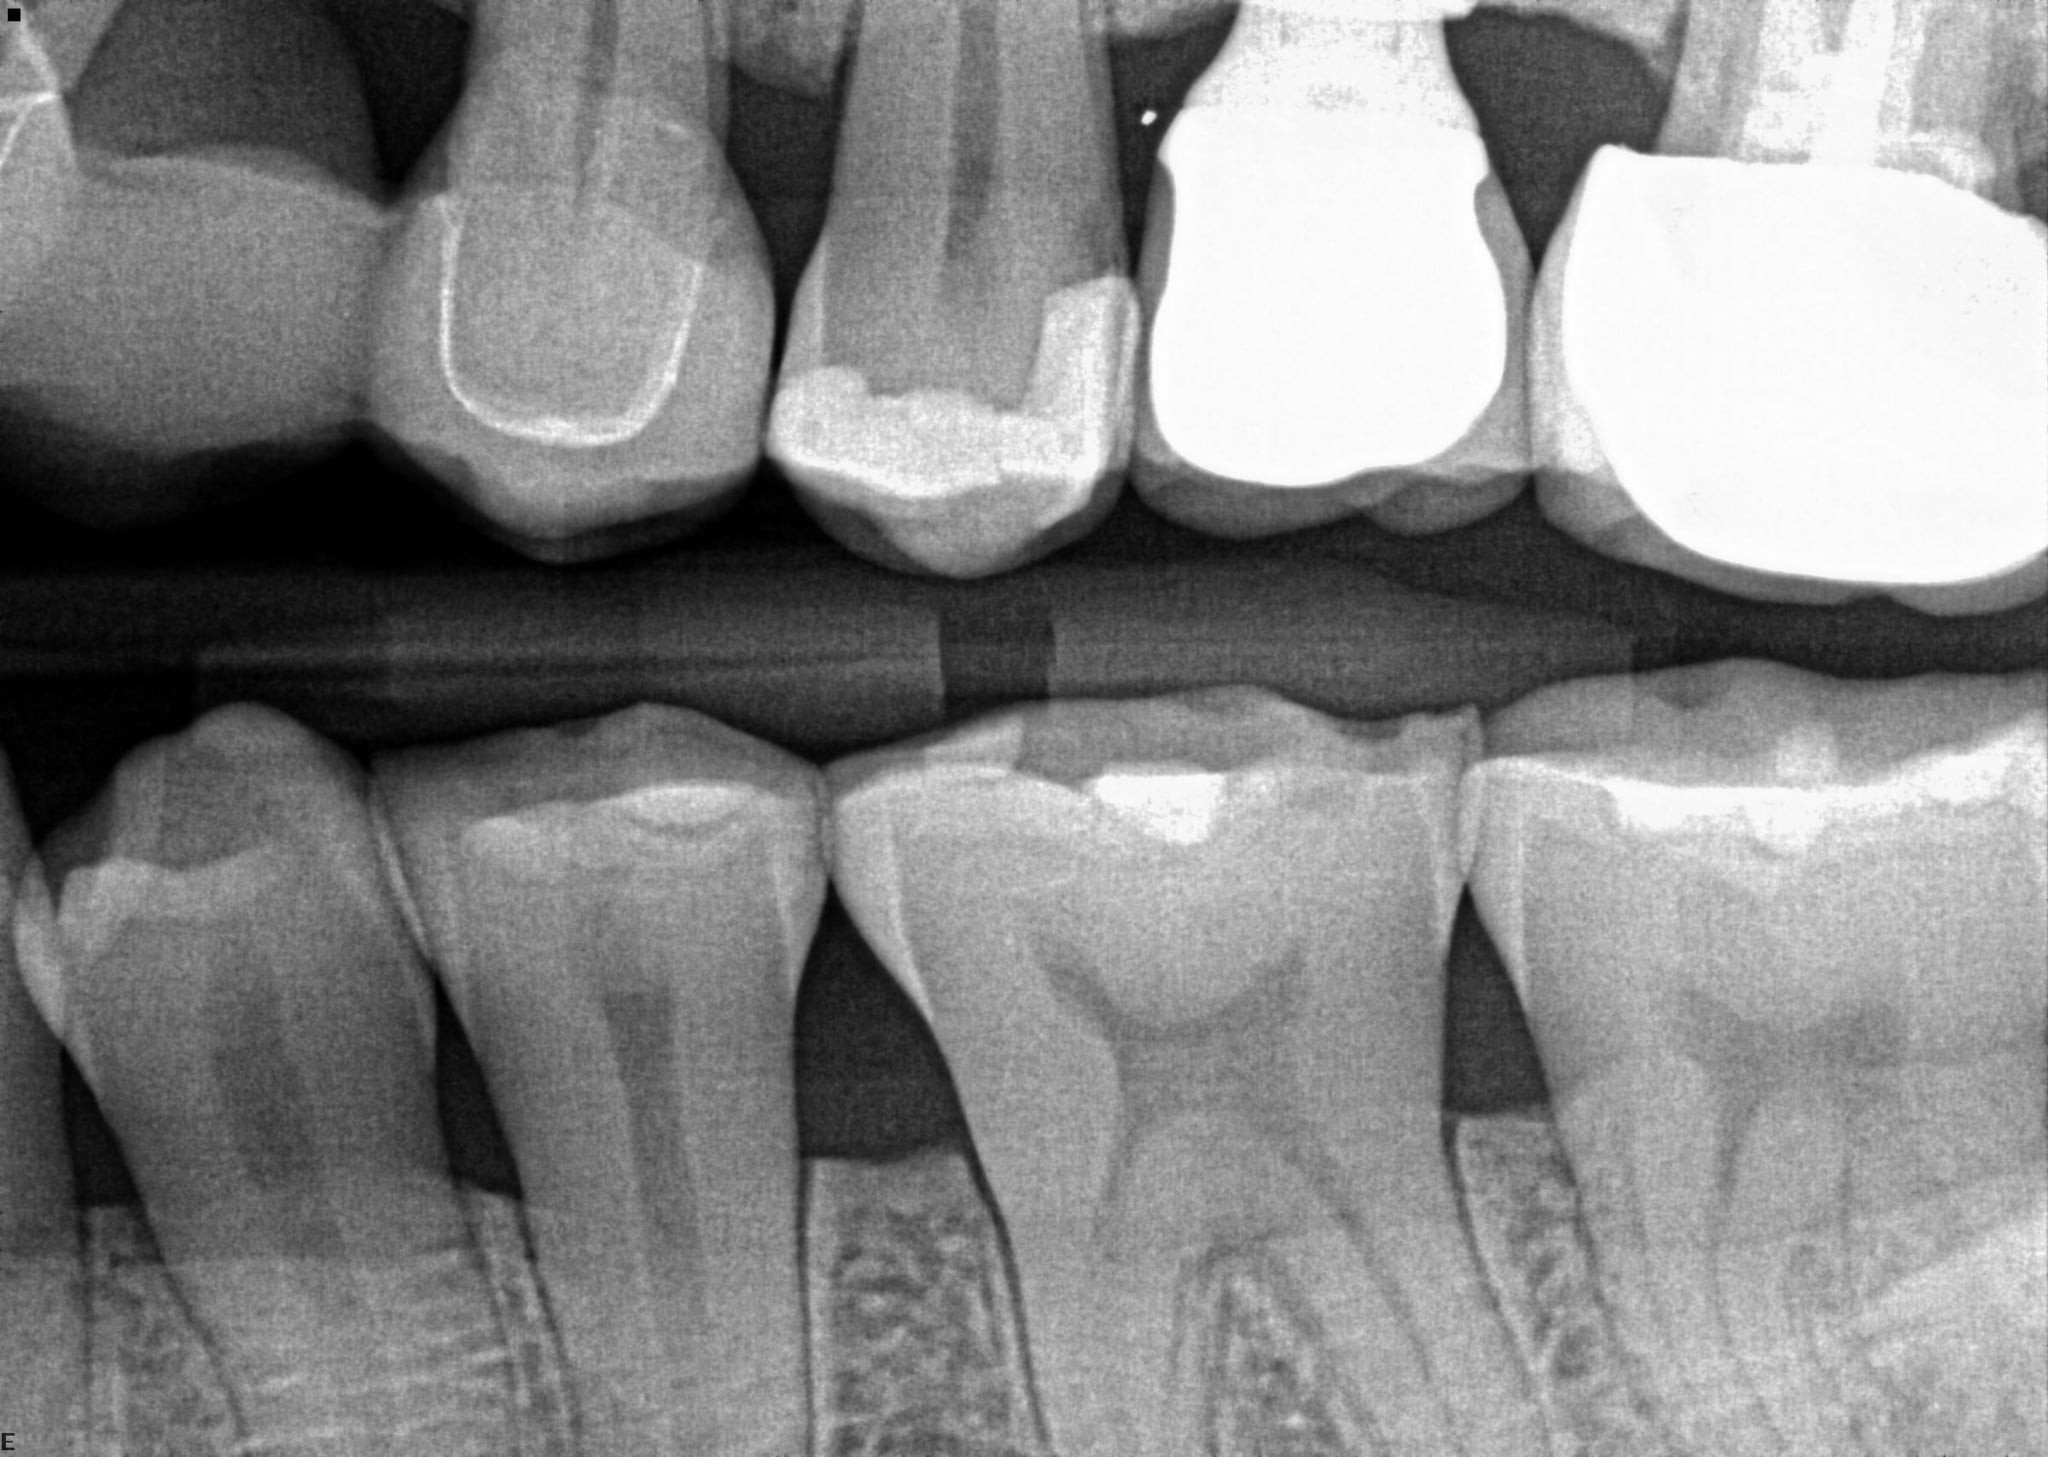

2. In the X ray bellow for which jaw periodontal bone loss is evident?